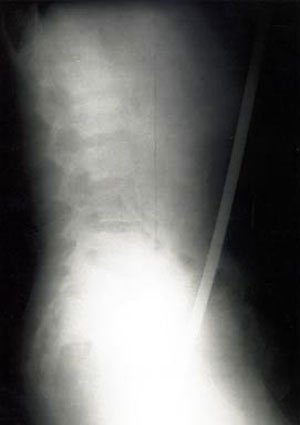

3. Người đàn ông này đã dẫm phải chiếc đinh khi đang đi dép xăng-đan: